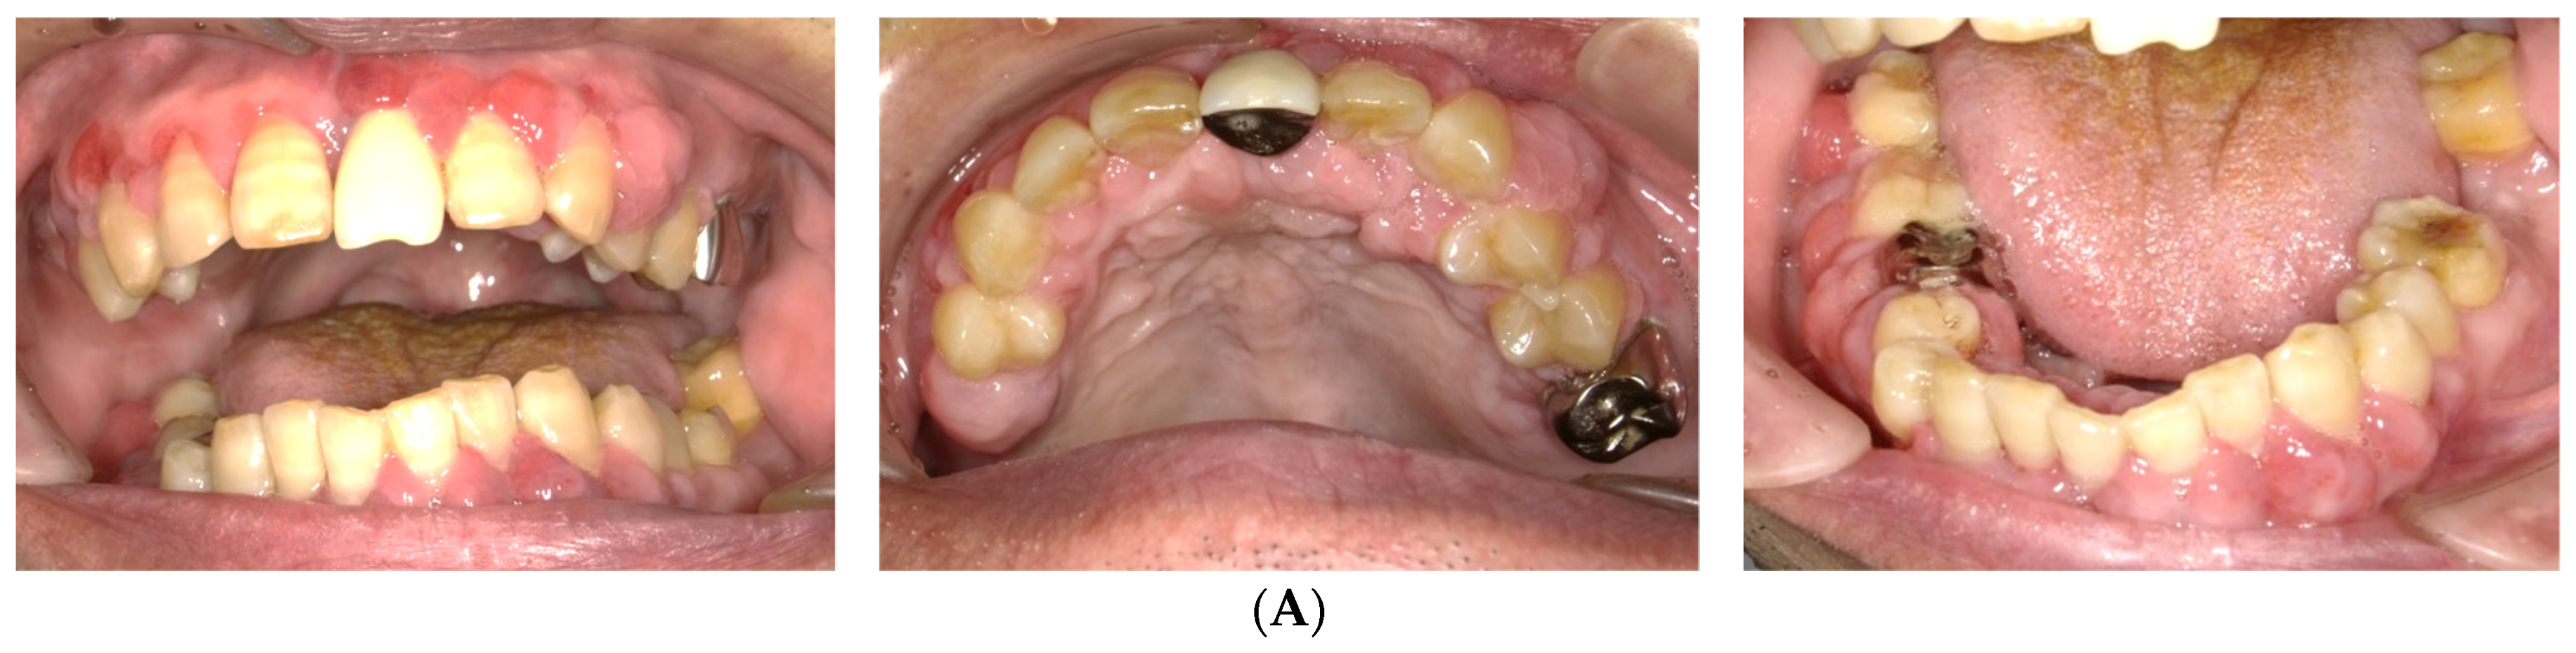

2.1. Day 1: First Examination